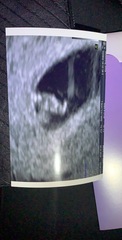

I had my early scan at EPU this morning following more spotting. I'm so pleased that everything is ok. Baby is in the right place and has a strong heartbeat. No explanation for the spotting but apparently it's positive that it's pink as opposed to brown.

Midwife was lovely and has pushed my dates back by a week, so I'm approx 6+2 now. They said that if the spotting continues or gets worse to go back. But at the minute there's nothing to worry about!

Here's my scan pic - baby is the top blob 🙈